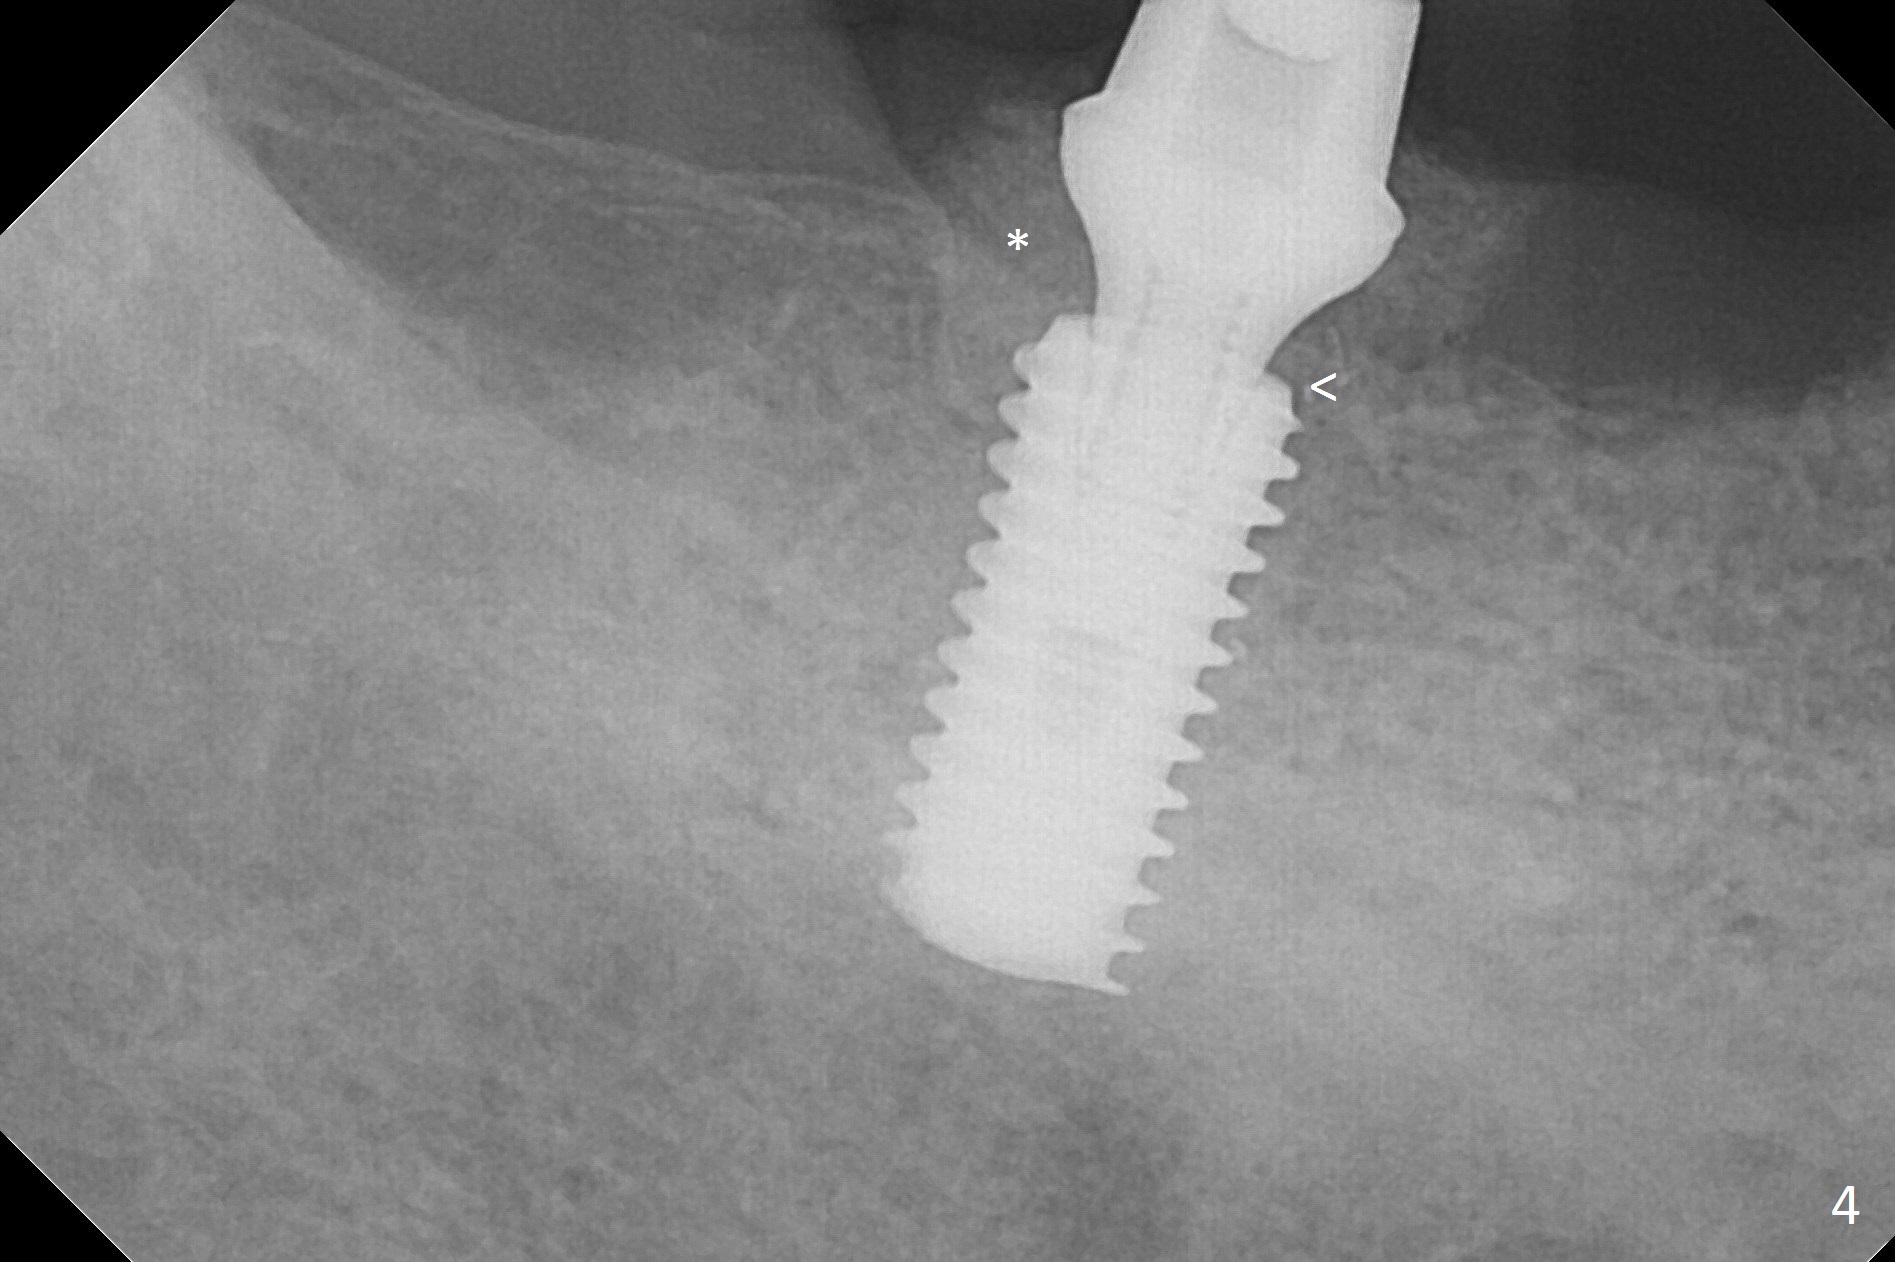

There are 2 challenges associated with #31 implant placement: indistinct Inferior Alveolar Canal (Fig.1-4) and difficulty in fabrication of a provisional (Fig.5).  After placing a 5.5x13 mm implant (Fig.3 supracrestal (<)), it is removed for apical resection for ~ 2 mm; when it is reseated, it is subcrestal (Fig.5 <).  A simplified temporary provisional (Fig.5 P) is fabricated around a 6.5x4(4) mm abutment (A) without adapting the lower RPD.  The patient is advised not to wear the latter.  When the socket heals, there will be 2 options: no provisional or a new one.  The latter should have good retention to the abutment and no contact with the lower RPD in and out.